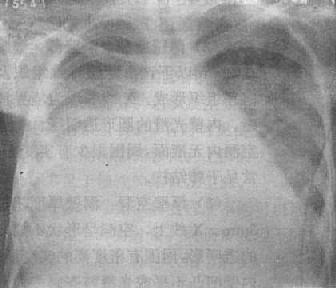

(2)液气胸:胸腔内液体与气体并存,为液气胸(hydropneumothorax)。可因胸腔积液并发支气管胸膜瘘外伤、手术后以及胸腔穿剌时漏进气体而引起,也可先有气胸而后出现液体或气体与液体同时出现,明显的液气胸立位检查时可表现为横贯胸腔的液面,液面上方为空气及压缩的肺(图3-1-17)。气体较少时,则只见液面而不易看到气体。如有胸膜粘连,可形成多房性液气胸。

液气胸

图3-1-17 液气胸

左肺萎陷,靠近纵隔,肺外有透明区,其中未见肺纹

理,下部致密,其上缘平直